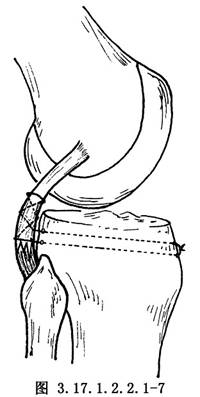

如半月板和交叉韌帶有損傷,儘可能予以修補,然後再自後側開始修補外側結構。①如有後外側關節囊撕脫,將其牽到脛骨關節面下方,用圓針引絲線穿過脛骨關節面下的鑽孔,由前到後縫合固定在脛骨上(圖3.17.1.2.2.1-4)。固定前將脛骨附着部的骨表面弄毛糙,或用骨刀做一新鮮骨創面,以保證後外側關節囊的固定。②有膕肌腱撕裂者,按損傷類型採用不同的方法。股骨附着部的膕肌腱撕裂,常伴有外側副韌帶自股骨上撕脫,可採用Bunnell縫合,通過股骨的鑽孔,捆紮在股骨內上髁的骨面上(圖3.17.1.2.2.1-5)。膕肌腱本身撕裂,將兩端用Bunnell縫合(圖3.17.1.2.2.1-6)。撕裂在肌肉內或肌腱連接部,用Bunnell縫合通過脛骨前外側近端Gerdg結節的骨孔,將肌腱附着到脛骨的後面(圖3.17.1.2.2.1-7)。③修補外側副韌帶。對外側副韌帶的撕裂先明確撕裂的部位,對股骨附着部的撕脫可採用U形釘、螺釘固定,或將斷端用Bunnell縫合,通過股骨的鑽孔捆紮在股骨內上髁上。外側副韌帶從腓骨頂點撕裂則伴有股二頭肌腱、弓狀韌帶及腓側副韌帶附着點的複合撕脫,應一併修復,在腓骨頭穿孔,粗線縫合固定。伴有骨片撕脫,可用1枚螺釘或交叉克氏針固定骨片(圖3.17.1.2.2.1-8)。如爲韌帶本身的撕裂,找出兩斷端拉緊後屈膝30°位,用不吸收的絲線對端或重疊縫合(圖3.17.1.2.2.1-9)。並將外側緣向前推進,縫合在外側正中關節囊的後緣和外側副韌帶的後緣。還可應用股二頭肌腱、腓腸肌腱和髂脛束加強修補。